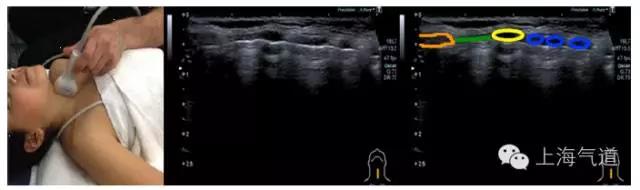

图5 a. 将探头继续下移,蓝色为低回声的气管环前壁,绿色为多层环状结构的食道,红色为颈动脉。b. 将探头继续下移,甲状腺影像逐渐消失